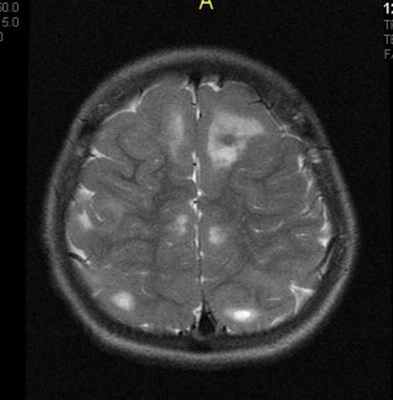

При подозрении на эту болезнь обязательно следует проводить МРТ головного мозга. При этом в головном мозге выявляются характерные МРТ-признаки туберозного склероза: корковые и подкорковые узлы (туберсы), субэпендимальные узелки (гамартомы), а также различные изменения белого вещества – очаговые и кистозные.

МРТ головного мозга при туберозном склерозе. Участки изменения МР-сигнала неправильной формы в коре и подкорковом белом веществе — так называемые корковые туберсы.